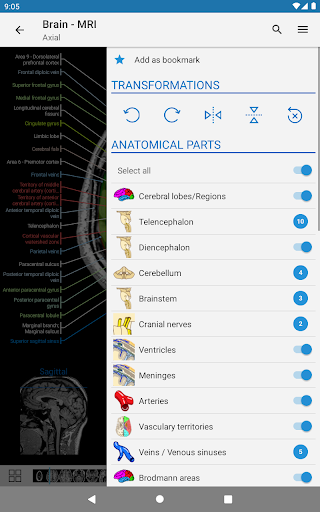

- Pilih label anatomi berdasarkan kategori

e-Anatomy memiliki lebih dari 26.000 gambar yang berisi serangkaian gambar dalam tampilan aksial, koronal, dan sagital serta radiografi, angiografi, gambar diseksi, bagan anatomi, dan ilustrasi. Semua gambar medis diberi label dengan cermat, lebih dari 967.000 label tersedia dalam 12 bahasa termasuk Terminologia Anatomica Latin.

IMAIOS e-Anatomy adalah atlas anatomi manusia untuk dokter, ahli radiologi, mahasiswa kedokteran, dan teknisi radiologi. Dapatkan cuplikan lebih dari 26.000 gambar medis dan anatomi secara gratis sebelum berlangganan atlas anatomi manusia terperinci kami.